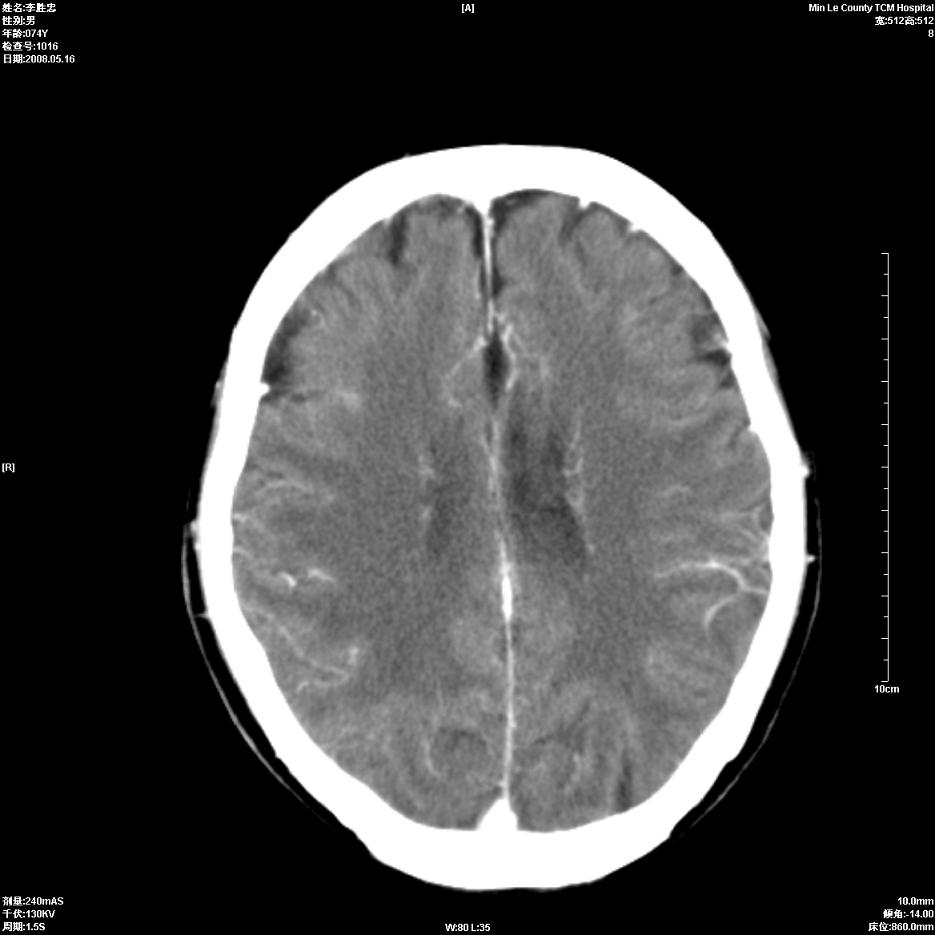

以下是引用深泽交通医院在2008-5-30 15:06:00的发言:[br]多发蛛网膜囊肿